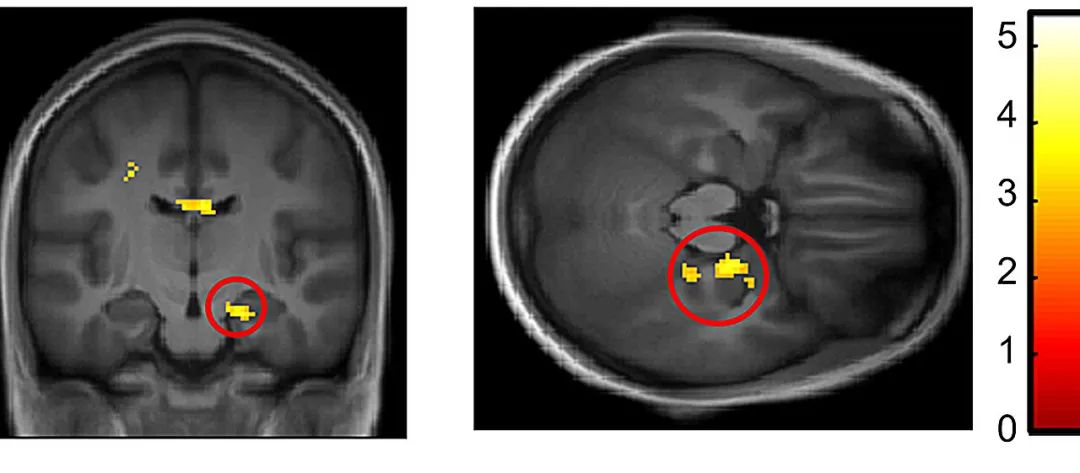

海马激活的MRI可视化

在对照组的个体中,运动后的表现伴随着海马体(对记忆至关重要的脑区)激活的增加,以及血液中内源性大麻素水平的增加。相反,在风险个体中,MRI 测量大脑活动显示在所有测试条件下,海马体神经元都出现过度激活。

Sophie Schwartz 教授解释说:“这一观察结果表明存在生理适应或补偿机制。他们的大脑需要调动更多的海马体来实现低于或类似于对照组的记忆得分。”